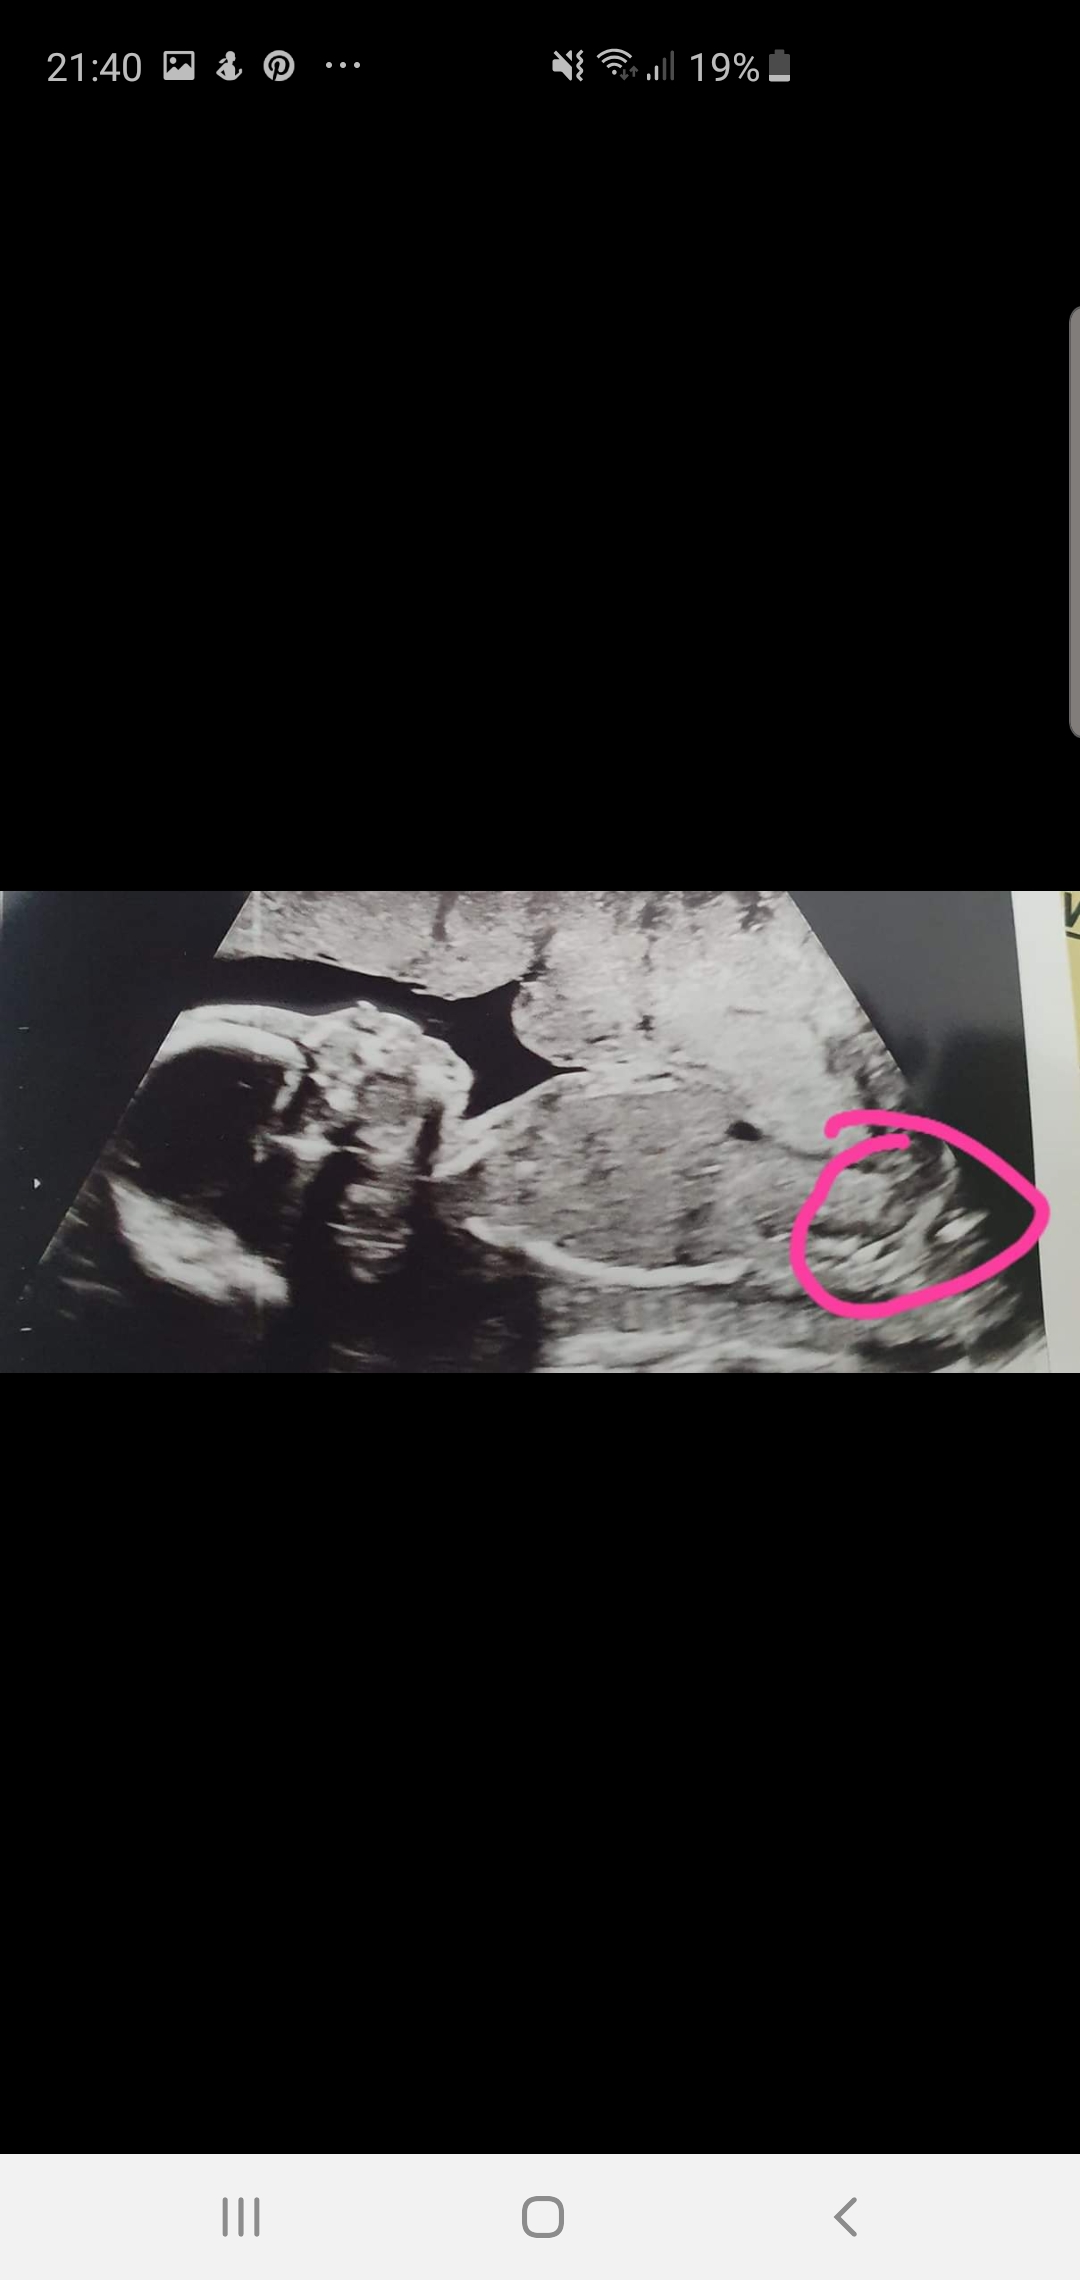

That's not a good nub shot. The thing you've circled is not the nub, I think it's the thigh bone.

The thing that is close to where your circle closes up at the top of the circle may be nub but there's not enough for me to guess on and I"m not sure it IS nub.

It is a very "busy" picture which can sometimes mean boy, but I am really really not too sure we've got the nub on this pic.